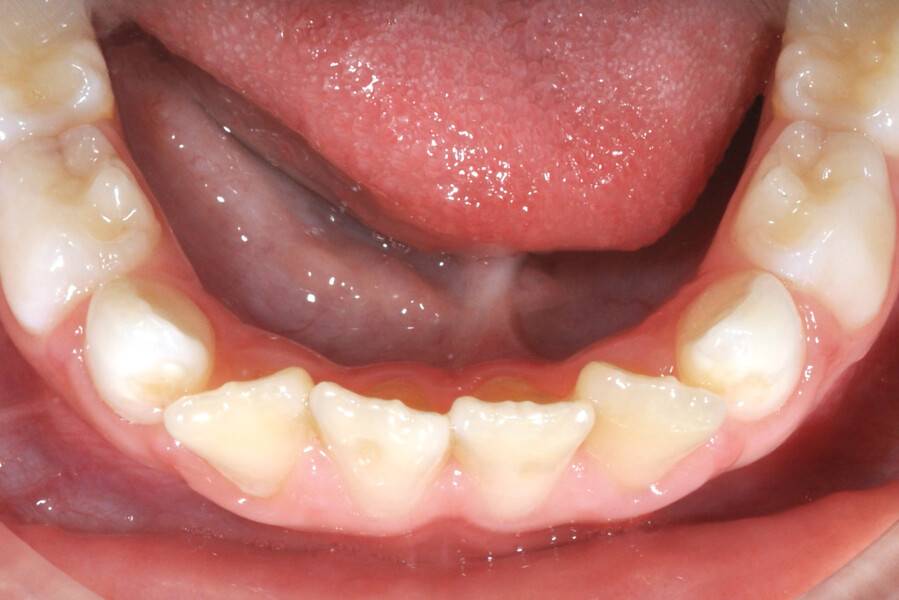

8 лет, девочка, жалобы на неправильный прикус и дефицит места зубам

Выполнено лечение с помощью LM-активатора на ночь